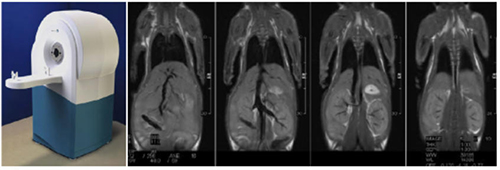

仪器型号:

MRS 3000™ Series

主要特点:

可针对小动物(小鼠)进行形态学、波谱学和功能影像等方面的前沿性研究,具有优越的软组织对比、高空间分辨率、允许多通道成像、稳定性高,是目前动物模型研究中不可或缺的工具之一。具有多方向切面影像、体位成像、心、血管动态成像、对比剂成像、灌注成像等多种成像方式。

服务内容:

腹部扫描(T1W,T2W,DWI,DTI等序列扫描)。